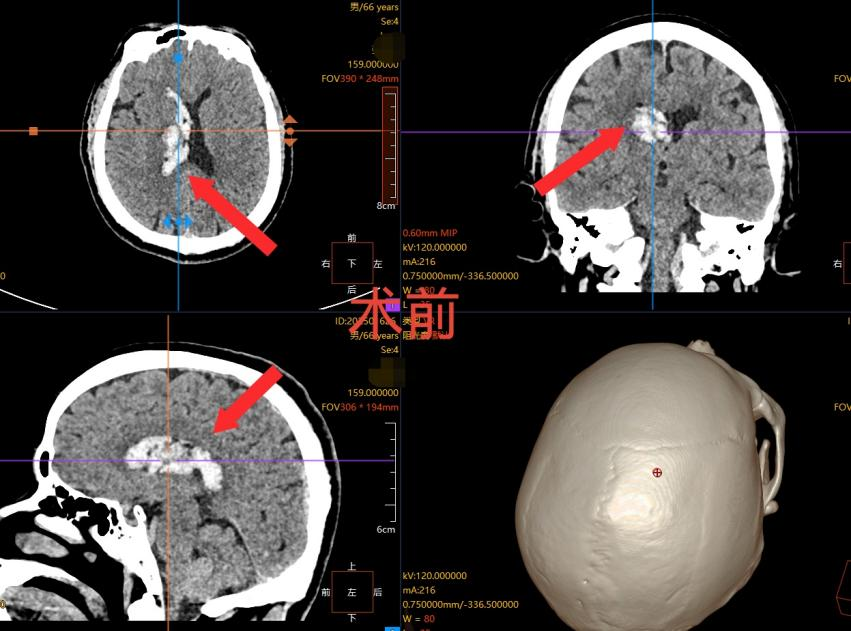

66 岁的张先生在家中突发剧烈头痛,伴随频繁呕吐,家人察觉情况危急,立即将其送往我院就诊。经头部 CT 检查,张先生被确诊为 “右侧丘脑出血并破入脑室系统”—— 这是脑血管疾病中极具风险的类型。

(箭头处白色信号为脑出血形成的血肿)